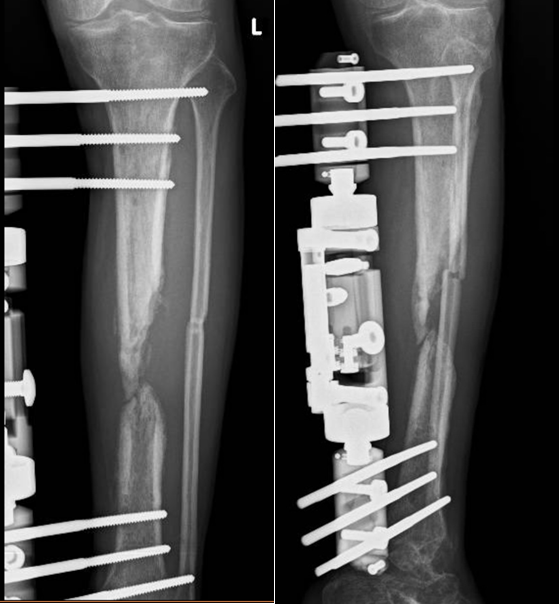

Hình XQ xương sau mổ và vạt da sống tốt sau 10 ngày

XQ xương sau mổ và vạt da sống tốt sau 10 ngày